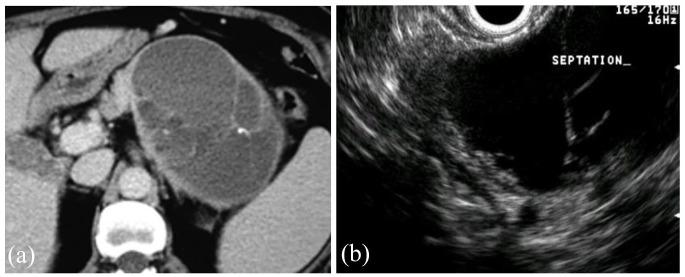

在过去十年中,胰腺囊肿的患病率显著上升,部分原因是横断面成像的质量和频率提高。虽然大多数囊肿不会发展为癌症,但少数会发展,需要进行随访。由于多种指南的建议各不相同,胰腺囊肿的管理可能既令人困惑又令人生畏。尽管指南的具体内容存在差异,但它们都认同几个高风险特征,在评估胰腺囊肿时,任何临床医生都应关注这些特征:存在壁结节或实性成分、主胰管扩张(或存在主胰管内乳头状黏液性肿瘤)、胰腺囊肿大小≥3 - 4厘米,或胰腺囊肿液抽吸细胞学检查呈阳性。其他需要考虑的重要标准包括囊肿快速生长(≥5毫米/年)、血清糖类抗原19 - 9水平升高、新发糖尿病或被认为与囊性病变相关的急性胰腺炎。